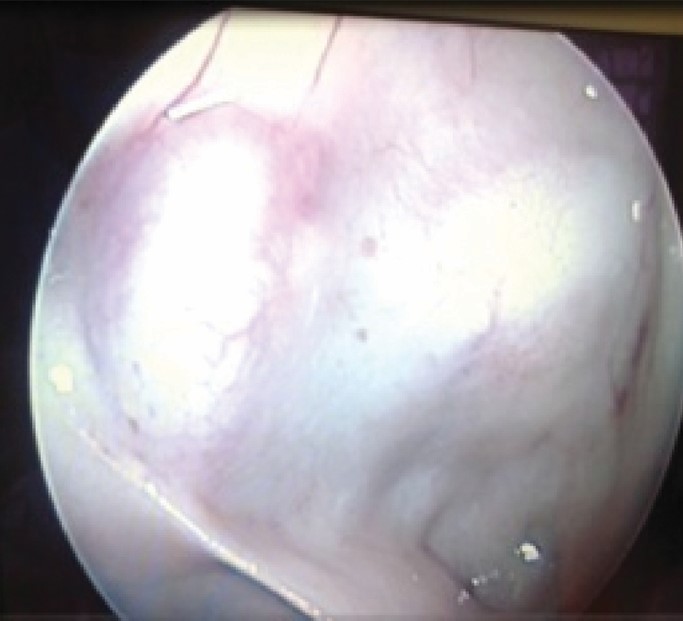

ВВЕДЕНИЕ В настоящее время в связи с распространением лучевых (МРТ, КТ) и визуальных (эндоскопия) методов диагностики наблюдается увеличение количества случаев изолированного сфеноидита [1, 2, 3]. Удельный вес изолированного сфеноидита в общей структуре заболеваний околоносовых пазух (ОНП), по данным литературы, составляет не более 5% [4, 5, 6]. Однако абсолютные цифры с учетом огромного количества случаев воспалительной патологии ОНП могут быть весьма значительными. В структуре синуситов все больше резистентных (устойчивых к лечению) форм, в том числе грибковых [7]. Данные о распространенности патологии весьма скудные, в структуре статистической отчетности стационаров и поликлиник сфеноидит как самостоятельная нозологическая форма отражается крайне редко. В то же время относительно невысокая распространенность нередко обусловливает пассивную позицию специалистов при дифференциальной диагностике поражений клиновидной пазухи (КП). Основное место в дифференциальной диагностике у данной группы пациентов занимают компьютерная томография (КТ) и магнитно-резонансная томография (МРТ). Однако трактовка результатов исследований не всегда однозначна и может приводить как к гипердиагностике, так и, наоборот, к гиподиагностике сфеноидита, выражающейся в недооценке данных лучевой диагностики и обьективной картины и нередко приводящей к развитию хронических и осложненных форм. Пациенты направляются к лор-врачу только после длительного, безуспешного лечения у специалистов смежных специальностей, что влечет высокий уровень гиподиагностики сфеноидита и наличие осложненных форм [8]. Дифференциальная диагностика патологического процесса в пазухе на дооперационном этапе чрезвычайно важна, поскольку необдуманное вмешательство может вызвать тяжелые и даже фатальные осложнения [9, 10]. От 5% до 30% всех изолированных поражений клиновидной пазухи составляют пациенты с неинвазивной грибковой формой [11, 12]. Для хронического сфеноидита характерно латентное (скрытое) течение, которое не всегда диагностируется на ранних стадиях [13, 14]. По данным ряда исследователей, частота патологических находок в клиновидной пазухе при аутопсии лиц, прижизненный диагноз «сфеноидит» у которых не был установлен, составляет от 10% до 68% [15, 16]. Очень важно изучение вопросов ремоделирования в клиновидной пазухе, в том числе явлений остеита при грибковых формах [17]. Осложненное течение изолированного сфеноиди-та - нередкое явление, при этом основным фактором развития осложнений является несвоевременная диагностика. Наиболее часто встречаются осложнения, связанные с вовлечением в патологический процесс глазодвигательных нервов, в особенности VI пары - n. abducens [4, 9, 16]. В литературе можно встретить наблюдения инвазивных, генерализованных форм грибкового сфеноидита с быстрым развитием офтальмологических, интракраниальных и системных (септических) осложнений [7, 12, 14]. Тактика лечения при изолированных поражениях клиновидной пазухи, по данным литературы, различная. Часть авторов считает наличие изолированного сфеноидита, особенно грибковых форм, мукоцеле, абсолютным показанием к операции. Другие авторы при отсутствии осложнений начинают с консервативной терапии [1, 3, 11, 12]. Задачей хирургического лечения у таких пациентов является не только купирование воспалительного процесса, но и создание условий для адекватной вентиляции пазух и предотвращения возможного рецидива. В то же время вопросы дифференцированного подхода к хирургическому лечению недостаточно освещены в научной литературе и носят преимущественно описательный характер. ш ЦЕЛЬ Провести анализ случаев изолированного поражения клиновидной пазух и выявить основные особенности и ошибки при дифференциальной диагностике на догоспитальном этапе. ш МАТЕРИАЛ И МЕТОДЫ В работе приведены данные о лечении 58 пациентов с изолированным поражением клиновидной пазухи, которые находились на стационарном лечении в ГБУЗ НОКБ им. Н.А. Семашко (кафедра болезней уха, горла и носа ФГБОУ ВО «ПИМУ» Минздрава РФ) в период 2015-2018 гг. Возраст пациентов - от 18 до 68 лет. Средний возраст пациентов с изолированным сфеноидитом составил 43 года, среди них превалировали женщины до 35 лет. Гендерное распределение было следующее: мужчины - 21 (30,7 %), женщины - 37 (69,3%). Давность заболевания составила 26±19 дней. Всего в клинике в данный период наблюдались 118 пациентов с различными формами поражения клиновидной пазухи, у 60 пациентов поражение КП наблюдалось как проявление хронического риносинусита (с полипами и без), то есть имело место сочетанное поражение нескольких или всех околоносовых пазух, и данные наблюдения не были включены в исследование. Критерии включения в исследование: рентгенологические (КТ, МРТ) признаки патологического процесса в клиновидной пазухе, специфическая и неспецифическая симптоматика, латентное течение сфеноидита, отсутствие патологического процесса в других околоносовых пазухах. Критерии исключения: сочетанное поражение других групп околоносовых пазух, нозокомиальный сфенои-дит. Такие состояния, как искривление носовой перегородки, вазомоторный/аллергический ринит, гипертрофия носовых раковин, mnchabullosa средних носовых раковин критериями исключения не являлись. Пациенты с впервые установленным диагнозом составили 85% от общего числа, 15% наблюдений - рецидивные формы заболевания, в том числе 5 пациентов были после ранее проведенного оперативного вмешательства (таблица 1). Морфологическая форма Количество наблюдений Полипозный процесс 15 (25,8%) Киста 18 (31%) Мукоцеле 5 (8,6%) Грибковый сфеноидит 12 (20,6%) Инвазивный грибковый сфеноидит 2 (3,4%) Менингоцеле 4 (6,8%) Новообразование 2 (3,4%) Таблица1. Распределение по виду патологического процесса Table 1. Distribution by the type of pathological process При поступлении в стационар проведено обследование пациентов в следующем объеме: клинические анализы, консультации смежных специалистов - невролога, нейрохирурга, офтальмолога (в зависимости от клинических проявлений). Всем пациентам проводилась предоперационная эндориноскопия. При подготовке к оперативному лечению оценивалось наличие у пациента сопутствующих заболеваний, течение которых проявляется симптоматикой со стороны ОНП и может в значительной степени оказывать влияние на течение патологического процесса в полости носа и ОНП: бронхиальная астма, аспириновая триада, персистирующий или интермиттирующий аллергический ринит, а также комбинация данных заболеваний. ш ОБСУЖДЕНИЕ И РЕЗУЛЬТАТЫ В большинстве случаев причиной обращения за помощью был цефалгический синдром. Все пациенты с болевым синдромом первоначально проходили обследование у невролога либо терапевта, им выполнялось МРТ-исследование на догоспитальном этапе. В данной группе пациентов (n=21, 36,2%) 9 человек были направлены к оториноларингологу сразу после получения данных МРТ. 12 пациентов проходили дальнейшее консервативное лечение у невролога либо не получали никакого лечения, несмотря на очевидные данные МРТ-исследования. После МРТ-исследования уточняющее КТ-исследование было назначено только 3 пациентам. Остальные пациенты были направлены в стационар с результатами МРТ. Таким образом, в рамках нашего исследования можно говорить о превалировании МРТ-диагностики в догоспитальном обследовании и игнорировании специалистами КТ-исследования. Симптоматическая картина у исследуемых пациентов весьма вариабельна: от латентных бессимптомных форм до тяжелых цефалгических и офтальмологических проявлений. Мы наблюдали определенную взаимосвязь между симптоматическими проявлениями и морфологической формой заболевания (таблица 2). В целом манифестирующая ринологическая симптоматика наблюдалась не более чем в трети наблюдений. В остальных ситуациях мы наблюдали либо неспецифическую симптоматику (цефалгические и/ или офтальмоплегические проявления), либо бессимптомное течение. Латентные формы поражений КП, когда патологический процесс выявлен случайно при МРТ/КТ-обследовании по другим причинам, составили около 20% от всех наблюдений. Чаще всего это были поражения в виде кисты клиновидной пазухи и мукоцеле (рисунок 1), реже бессимптомное течение наблюдалось при грибковой форме поражения и менингоцеле (рисунки 2, 3). Хирургическое лечение. Всем пациентам проводилось хирургическое лечение, после тщательного анализа КТ-томограмм для уточнения варианта строения клиновидной пазухи и наличия анатомических вариантов строения (клетки Оноди, дигисценции канала внутренней сонной артерии, зрительного нерва и т.д.) (рисунки 4а, 4б). Все оперативные вмешательства выполнялись под общим обезболиванием. Применялись следующие доступы: трансназальный, расширенный трансназальный, трансэтмоидальный, доступ по методике Bolger Box, транскрыловидный (в одном случае) (таблица 3, фото 5, 6). Расширенный доступ (Wormald PJ. 2005, Palmer J.N. 2013) в отличие от традиционного с механическим расширением естественного соустья подразумевает выкраивание короткого (5-10 мм) назосептального лоскута Морфологическая форма Клинические симптомы Головная боль Постназальный затек Голово кружение Назальная обструкция Глазничные симптомы Полипозный процесс/ полипозно-гнойный + +++ - ++ - Киста - - - + - Мукоцеле ++ + - + - Грибковый сфеноидит ++ ++ + + + Инвазивный грибковый сфеноидит +++ ++ + + +++ Менингоцеле + + + - - Новообразование ++ + + - +++ «+» - степень выраженности симптома от + до +++. «-» - отсутствие симптома. Таблица 2. Симптоматические проявления Table 2. The symptomatic manifestation Рисунок 1. Мукоцеле клиновидной пазухи. Figure 1. Mucocele of the sphenoid sinus. Рисунок 2. Грибковый сфеноидит. 2.1 КТ (аксиальный срез); 2.2 Соустье обтурировано полипом. Трансназальный доступ; 2.3 - грибковые массы в пазухе. Figure 2. Fungal sphenoiditis. 2.1 CT (axial cross-section); 2.2 Anastomosis is obturated by a polyp. Transnasal access; 2.3 - fungal masses in the sinus. Рисунок 3. КТ (фронтальный срез). Остеит стенок клиновидной пазухи при грибковом синусите. Figure 3. CT (front section). Osteitis of the walls of the sphenoid sinus in fungal sinusitis. Рисунок 4а. Дигисценция канала внутренней сонной артерии. КТ-исследование. Figure 4a. Dehiscence of the internal carotid artery channel. CT study Рисунок 4б. Дигисценция канала внутренней сонной артерии. Эндоскопическая картина. Figure 4b. Dehiscence of the internal carotid artery channel. Endoscopic image. Таблица 3. Виды хирургических вмешательств Table 3. Types of surgical interventions слизистои ниже и медиальнее соустья пазухи на ножке с питанием от заднеИ септальноИ ветви крылонебной артерии с широким обнажением и резекцией передней стенки пазухи. При этом соустье мы расширяли при помощи бора. Данный способ упрощает задачу в том случае, если естественное соустье не визуализируется и технически не доступно и/или есть необходимость широкого открытия пазухи. Лоскут на питающей ножке используется для закрытия широкого костного дефекта, что способствует его дальнейшей эпите-лизации и минимизирует развитие в последующем остеита. Исследования ряда авторов свидетельствуют о том, что трансэтмоидальный и трансназальный доступ могут с одинаковым успехом применяться при Рисунок 5. 5a - грибковое тело латерального кармана клиновидной пазухи (КТ, аксиальный срез); 5b - расширенный трансназальный доступ (700 эндоскоп); 5c - КТ через 6 мес. после операции. Figure 5. 5a - fungal ball in the lateral “pocket" of the sphenoid sinus (CT, axial section); 5b - extended transnasal access (700 endoscope); 5c - CT in 6 months after operation. Рисунок 6. Менингоцеле клиновидной пазухи. 6а - МРТ (фронтальный срез); 6b - расширенный трансназальный доступ. Пластика ликворного дефекта после удаления менингоцеле (материал - жир). Figure 6. Meningocele of the sphenoid sinus. 6a - MRI (frontal section); 6b - extended transnasal access. Plasty of the liquor defect after the meningocele removal (the material - fat). Рисунок 7. Соустье через 1 год после расширенного доступа. Figure 7. Anastomosis 1 year after expanded access. Рисунок 8. Соустье через 3 года после расширенного трансназального доступа. Рисунок 9. Рецидив полипозно-гнойного сфеноидита через 6 месяцев после операции. причиной рецидива патологического процесса и потребовал проведения ревизионного вмешательства. В одном случае у пациента, которому ранее выполнена сфенотомия по поводу хронического сфеноидита, но не была вскрыта (распознана) клетка Оноди, в которой локализовалось грибковое воспаление, также потребовалась повторная операция. Figure 9. Recurrence of polypous-purulent sphenoiditis in 6 months after surgery. Figure 8. Anastomosis 3 years after expanded access. изолированном поражении пазухи. Трансназальный доступ более безопасен, чем трансэтмоидальный, и является методом выбора при изолированном поражении пазухи при условии, что патологический процесс в пазухе не требует широкой ревизии и/или создания достаточного по объему сообщения в тех ситуациях, когда велик риск рецидива. Осложнений в послеоперационном периоде не наблюдалось. На 5-7 сутки всем пациентам выполнялась эндориноскопия. В срок от 2 до 3 месяцев 11 пациентам выполнено контрольное КТ. Остальные пациенты (из отдаленных районов) не проходили контрольного осмотра. При выполнении расширенного доступа удалось добиться формирования стойкого, эпителизи-рованного соустья во всех случаях (рисунки 7, 8). При полипозно-гнойных формах сфеноидита наиболее часто наблюдались рецидивы заболевания, однако здесь требовалась только противовоспалительная терапия, в том числе орошение пазухи через сформированное соустье (рисунок 9). Частота развития спаечного процесса после вмешательств составила около 20%, при этом только в 3 наблюдениях рубцово-спаечный процесс явился ш ВЫВОДЫ Изолированный сфенои-дит в структуре пациентов, которым проводилось эндохирургическое лечение при патологии ОНП, составил 3% (около 30% от общего числа сфеноидитов). В стационаре пациенты с точно установленным диагнозом «изолированный сфеноидит» на догоспитальном этапе составили не более 12% от общего числа, что связано как с гиподиагностикой, пассивной позицией в отношении патологии клиновидной пазухи у врачей амбулаторного звена, так и с тактическими ошибками. Отмечено превалирование МРТ-диагностики в догоспитальном обследовании и игнорирование специалистами КТ-исследования. Основной метод лечения изолированного сфеноидита - хирургический. Наиболее часто применялся расширенный трансназальный доступ. Необходимо сочетание с медикаментозным лечением в послеоперационном периоде. Требуются дальнейшие исследования с целью изучения особенности/безопасности и клинической эффективности различных эндохирургических доступов. W Конфликт интересов: все авторы заявляют об отсутствии конфликта интересов, требующего раскрытия в данной статье.Об авторах